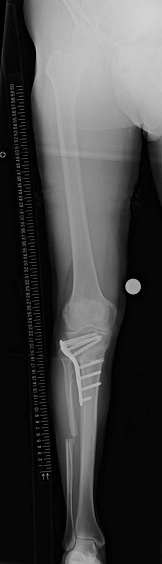

3. Closed wedge 高位脛骨骨切り術

4. 00121535_20200507_CR_0002_128